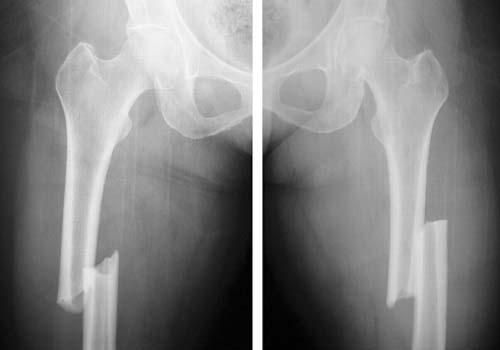

شکستگی ها

Fractures

بیماری های اطفال

Pediateric diseases

عکس های مرتبط

Photoes